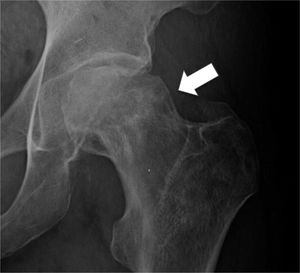

En el artículo: “de Pablo Márquez B, Ortiz Ciruela J. Abordaje del dolor de pelvis y cadera en Atención Primaria. FMC. 2025;32(10):553-60” apareció como figura 4 una imagen errónea. Se adjunta la correcta.